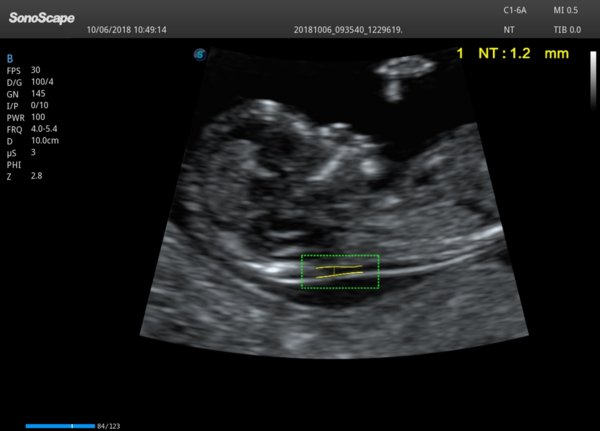

孕期11周至13周中,中国各级医院均会对孕妇开展超声NT检查。胎儿颈项透明层(nuchal translucency,NT)是指胎儿颈部皮肤与软组织之间最大无回声区。1992年Nicolaides等专家发现,胎儿NT增厚与染色体异常之间有明显相关性,这标志着影像学指标可以用来进行产前筛查。经过临床不断验证,NT被认为是唐氏综合征和其他染色体异常的最常见、最有效、敏感性和特异性最高的超声软标记。

从上面的介绍可以发现,对于产前检查来说,NT值意义重大。然而测量NT值对超声医生来说同样提出了很高的要求:根据英国胎儿基金会(FMF )推荐的测量标准规定,超声医生在测量NT值时应取胎儿正中矢状切面,胎儿呈自然体位,不俯屈或过度仰伸,图像应充分放大至胎头、颈及上胸占据屏幕3/4以上,游标放置于两条高回声线的内侧缘进行测量,这两条高回声线代表皮肤回声及颈椎表面软组织回声,其间部分即为NT,测量NT最宽处取值,并至少测量三次取最大值作为NT值。

NT测量的高要求给中国的产检带来了一定挑战,也对超声检查的设备提出了更高的要求,尤其是在二胎政策逐渐开放后,产科超声的工作压力逐渐增加,如何帮助临床医生快速测量NT值成为了超声设备的一个关键任务。开立医疗开发的Auto NT功能,可帮助医生快速准确获得NT值,在开立超声高分辨无失真前端放大技术的基础上,一键自动测量NT值,减少了人为测量差异,让产检更加简便、快捷、准确。

超声Auto NT功能展示